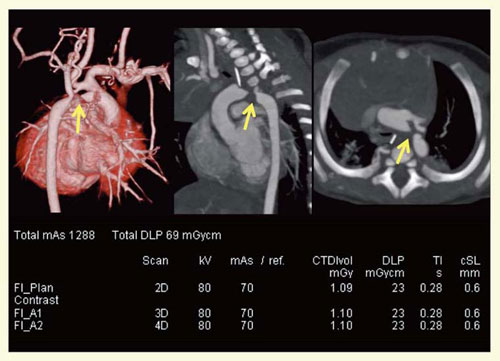

œ Ç—á5F‘å“®–¬—£’fÇC‘å“®–¬”x“®–¬‘‹C“®–¬ŠÇŠJ‘¶i}7j

0Î1‚©ŒŽC’jŽ™C‘Ìd3.4kgCS””160bpmBIRIS“±“ü‘O‚ÉŽB‰e‚³‚ꂽǗá‚Å‚ ‚邪CRawƒf[ƒ^‚©‚çFBP–@iB30fj‚ÆIRISiI30fj‚Å‚»‚ꂼ‚êÄ\¬‰æ‘œ‚ð쬂µ”äŠr‚µ‚½BIRIS‚ð—p‚¢‚½‰æ‘œ‚ÅSNR‚ª‰ü‘P‚µ‚Ä‚¢‚邱‚Æ‚ª‚í‚©‚éB

}7@Ç—á5F‘å“®–¬—£’fÇC‘å“®–¬”x“®–¬‘‹C“®–¬ŠÇŠJ‘¶i0Î1‚©ŒŽC’jŽ™j

œ Ç—á6F‘”xÖ¬ŠÒ—¬ˆÙíÇCC•œpŒãC”xÖ¬‹·ói}8j

0Î1‚©ŒŽŽži‘Ìd4kgjC0Î5‚©ŒŽŽži‘Ìd5.2kgjB“¯ˆêÇ—á‚ÅC‘”xÖ¬ŠÒ—¬ˆÙíÇ‚ÌpŒã‚É”xÖ¬‹·ó‚ÌÄ”‚ð”F‚ß‚½Š³Ž™‚Å‚ ‚éB0Î1‚©ŒŽŽž‚ÍIRIS“±“ü‘OC0Î5‚©ŒŽŽž‚ÍIRIS“±“üŒã‚ÌCTŒŸ¸‚ƂȂÁ‚½B‘Ìd‘‰Á‚à‚ ‚Á‚½‚ªCIRIS“±“üŒã‚Å‚ ‚èCŠÇ“d—¬‚ð20“‰º‚°‚ÄŽB‰e‚µ‚½‚ªCˆÈ‘O‚ÌŽB‰e‚É”ä‚ׂđ»F‚̂Ȃ¢‰æ‘œ‚ª“¾‚ç‚êCSD’l‚à‰ü‘P‚µ‚Ä‚¢‚éB

}8@Ç—á6F‘”xÖ¬ŠÒ—¬ˆÙíÇ